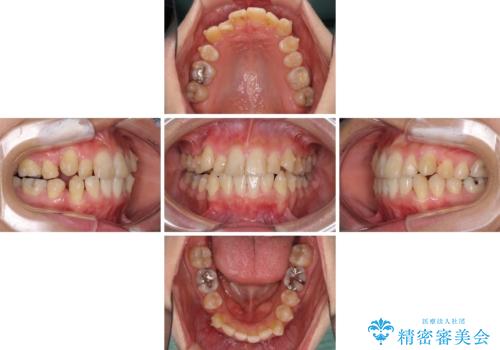

- 上下の八重歯を気にして来院された患者様です。

八重歯の後ろの歯を1歯抜歯し、補助装置(リンガルアーチ)を用いて八重歯の位置を改善し、その後インビザラインにより矯正治療を行うこととしました。

右側のみ上下小臼歯を抜歯したため、上下の正中が右にずれてしまう可能性があります。

また、元々右側は上下が咬み合っていないため、矯正をしても咬み合わないことも考えられました。